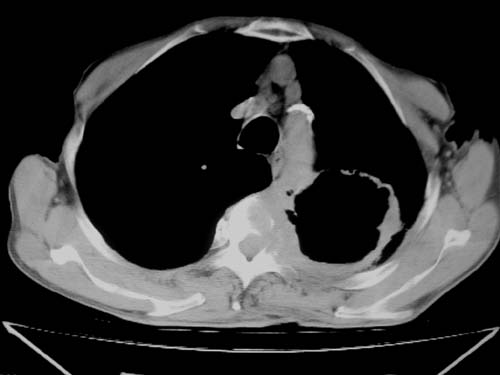

标题: CT19736:男,76岁,咳嗽,胸痛 [打印本页]

标题: CT19736:男,76岁,咳嗽,胸痛

支持左上肺周围型肺癌性并空洞形成伴胸椎转移。

左上沟癌空洞形成并胸椎转移。

考虑癌性空洞并胸椎转移。

空洞内壁有多发结节,支持癌性空洞。

支持左上肺周围型肺癌并空洞形成伴胸椎转移。z左下肺炎